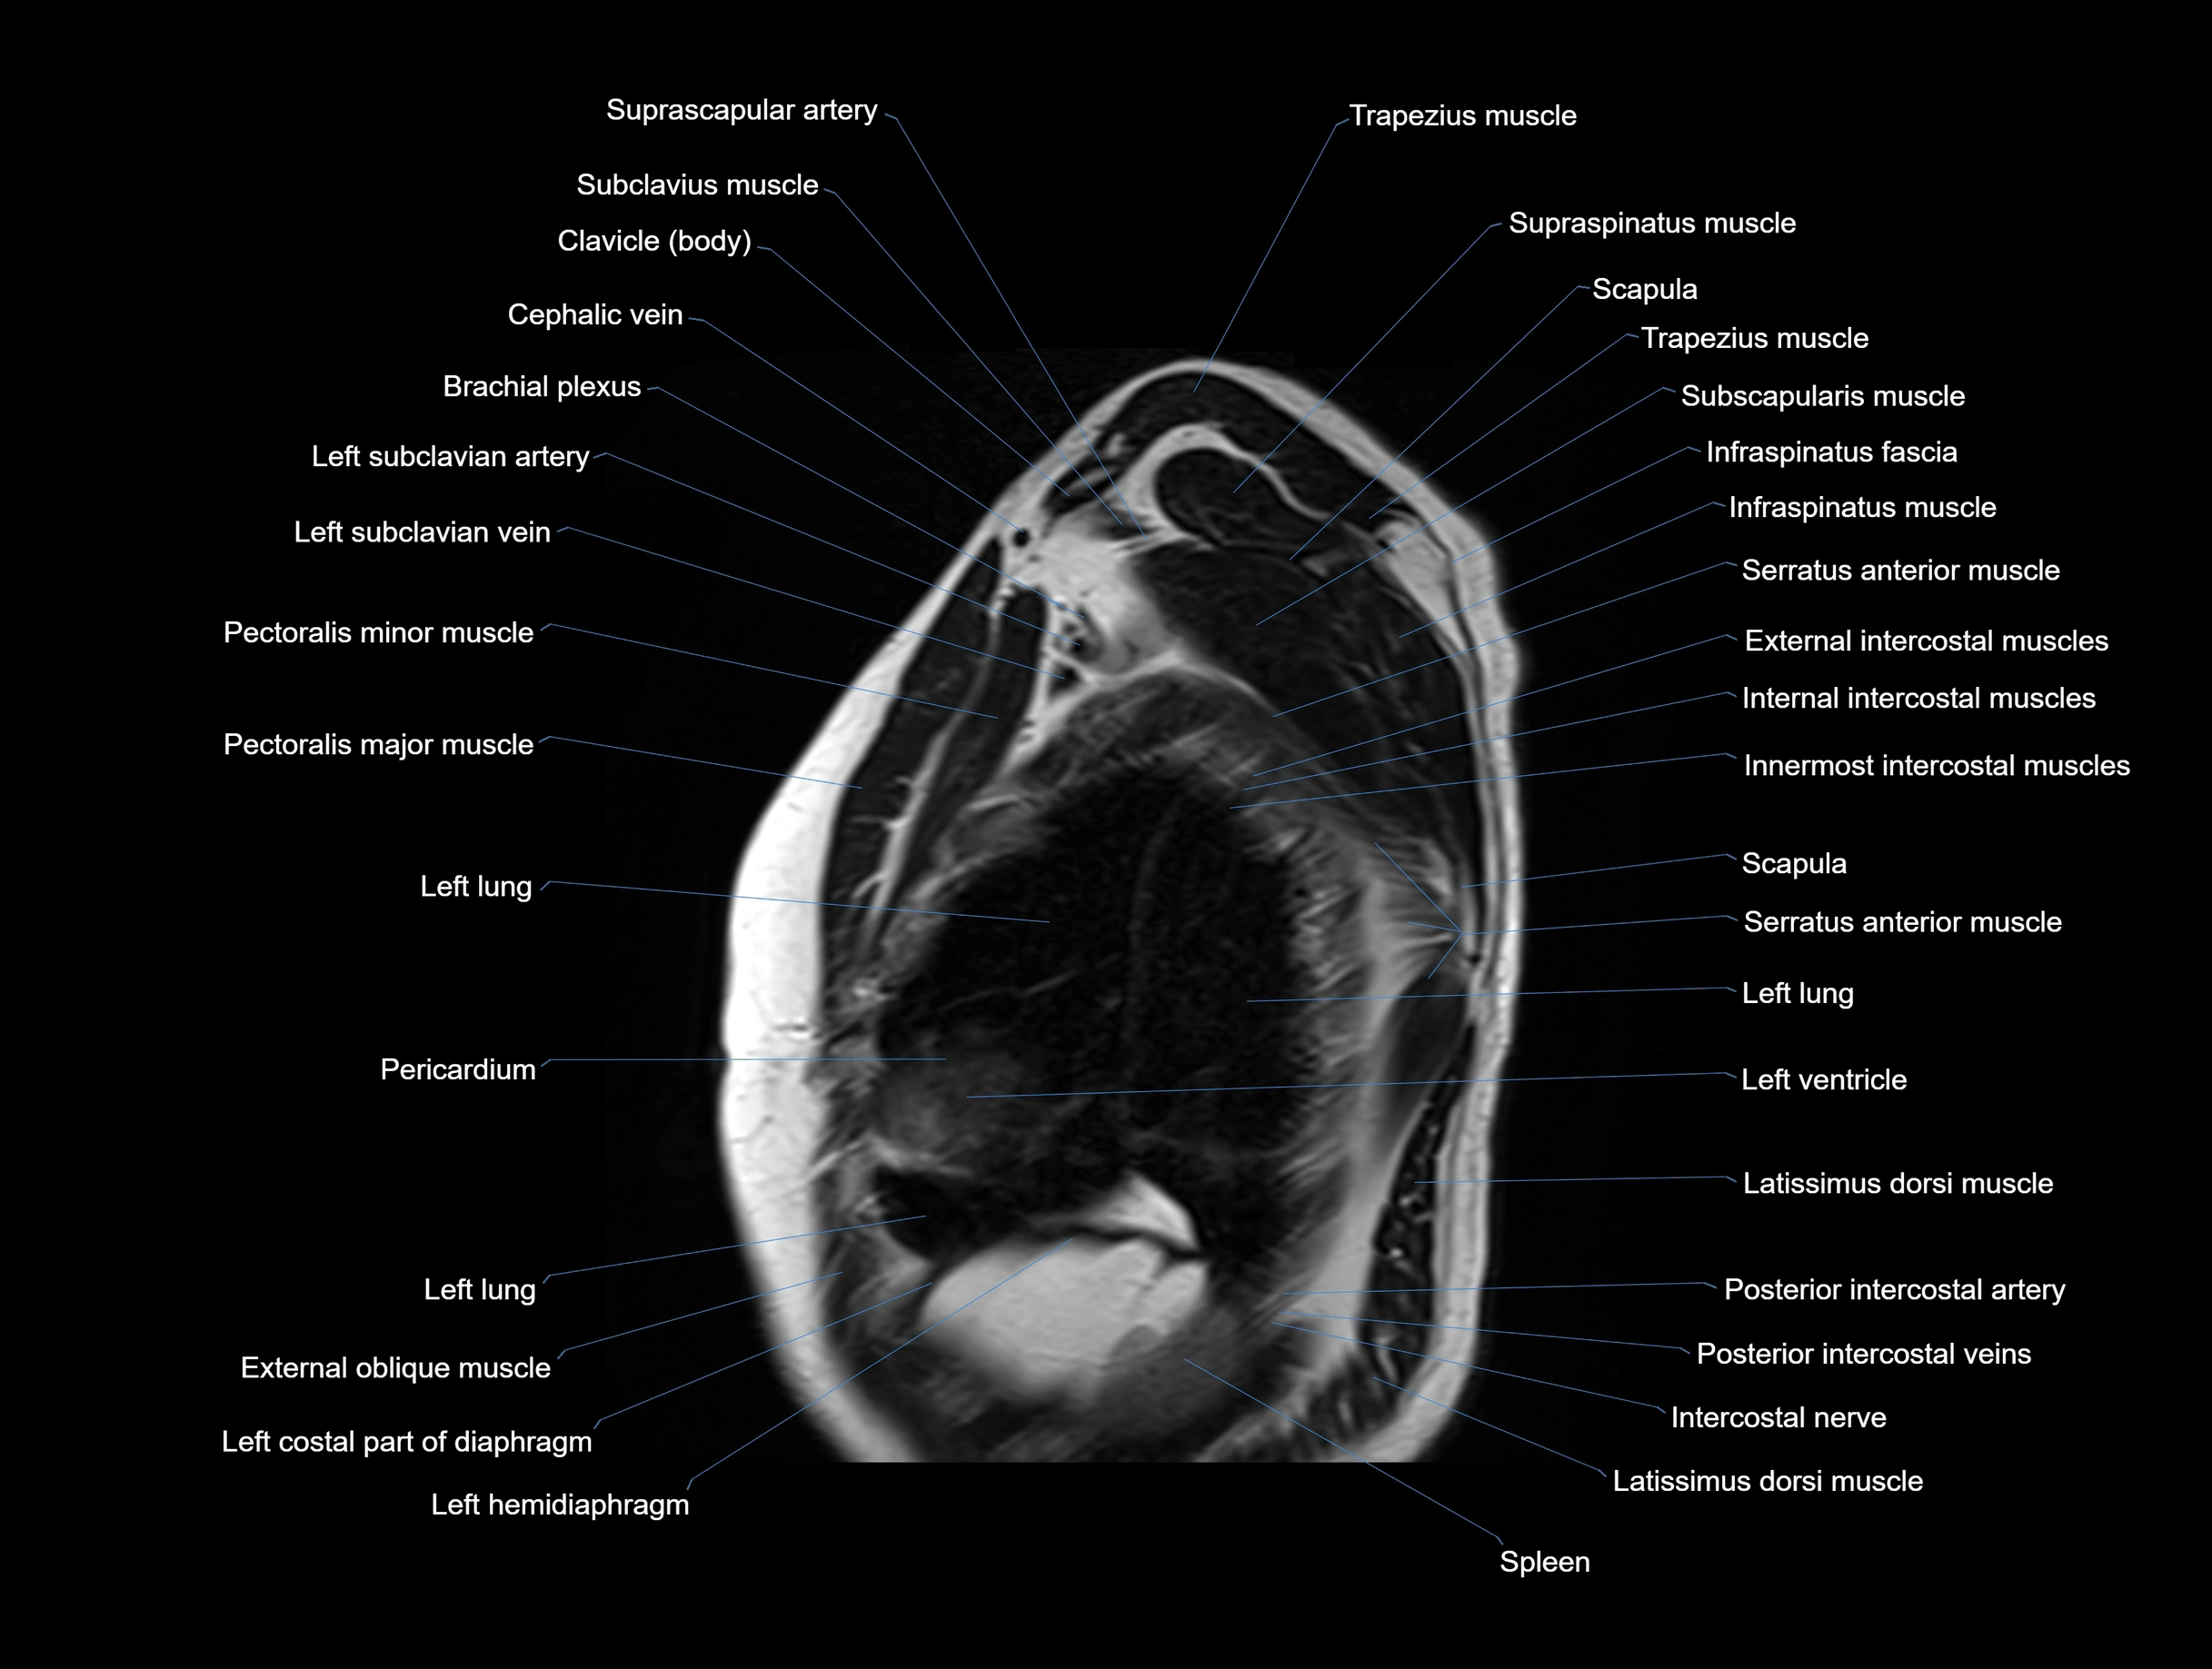

MRI images